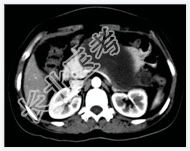

- [材料题] 患者,女性,31岁,反复上腹部疼痛1年,加重1天入院。B超示胰腺体尾部囊性病变,性质待定。行上腹部CT增强扫描。

- 简答题1、请问该患者诊断是什么?

- 简答题2、诊断依据是什么?

- 简答题3、鉴别诊断有哪些?